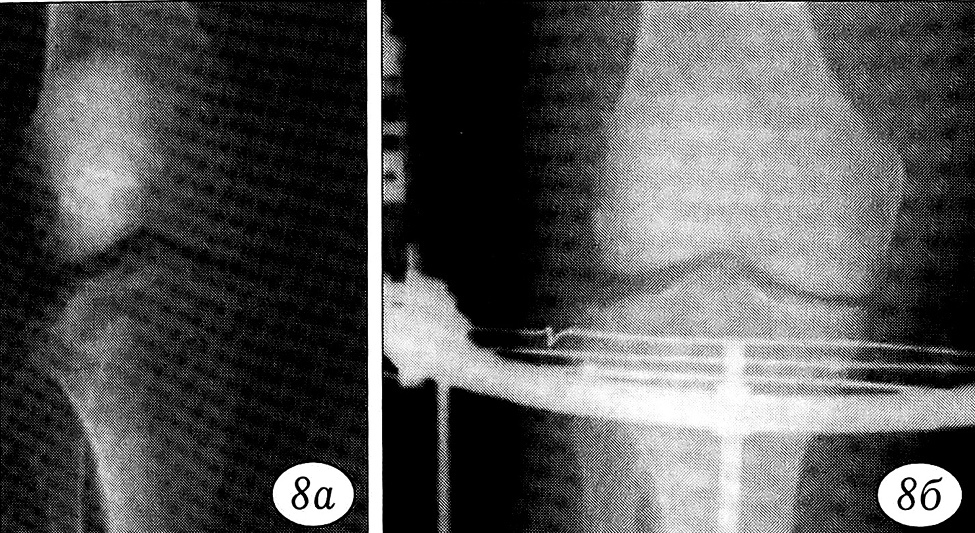

Рис. 2. Рентгенограммы больного 54 лет с переломом наружного мыщелка большеберцовой кости типа В1. a — до операции; б — после закрытой репозиции и фиксации в аппарате из одной дуговой опоры.